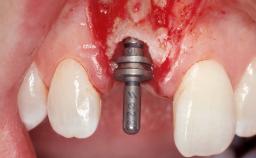

Late Flapless Placement of an Implant in a Maxillary Left Central Incisor Site

A 39-year-old male patient presented with a chief complaint of discomfort and gingival discoloration around his maxillary left central incisor. He was in good general health and was a non-smoker. His past dental history was significant because of the traumatic fracture of tooth 21 in a sporting accident at age 13. Initial dental treatment included endodontic therapy and a full-coverage restoration. The patient became symptomatic 5 years later, when structural failure of the tooth resulted in the dislodgment of the crown. Endodontic retreatment, apical surgery, and post-and-core restoration were performed.

Bone Augmentation Horizontal|Staged

Augmentation Materials Xenogenous|Membrane

Bone Volume Deficient horizontally, requiring prior grafting